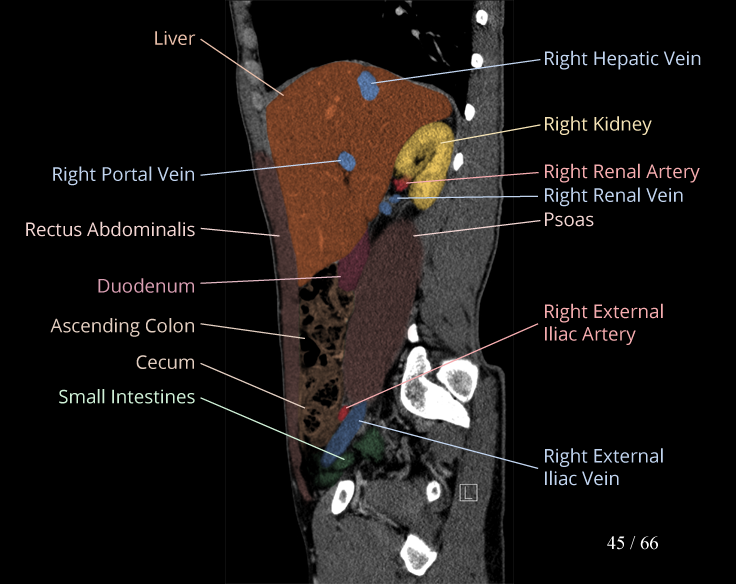

Body

Covers abdominal CT anatomy.